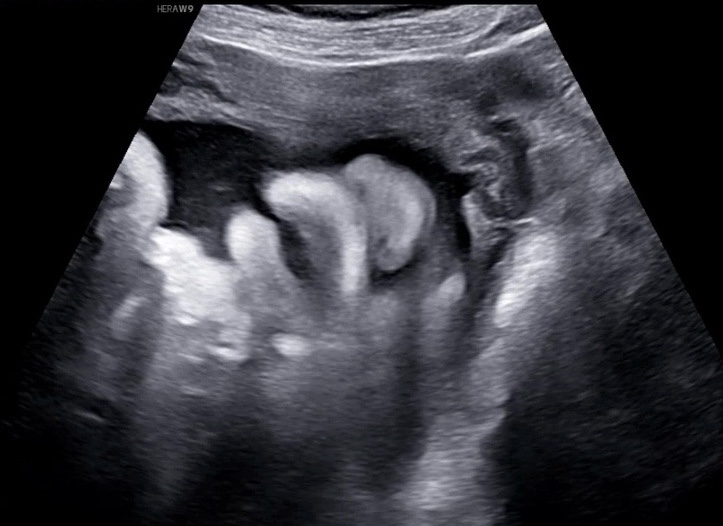

임신일기#9. 임신 40주차

임신 40주차의 일기 사실 40주까지 올지 몰랐는데 40주 4일인 오늘 출산을하고 병원에서 쓰는 40주일기 출...